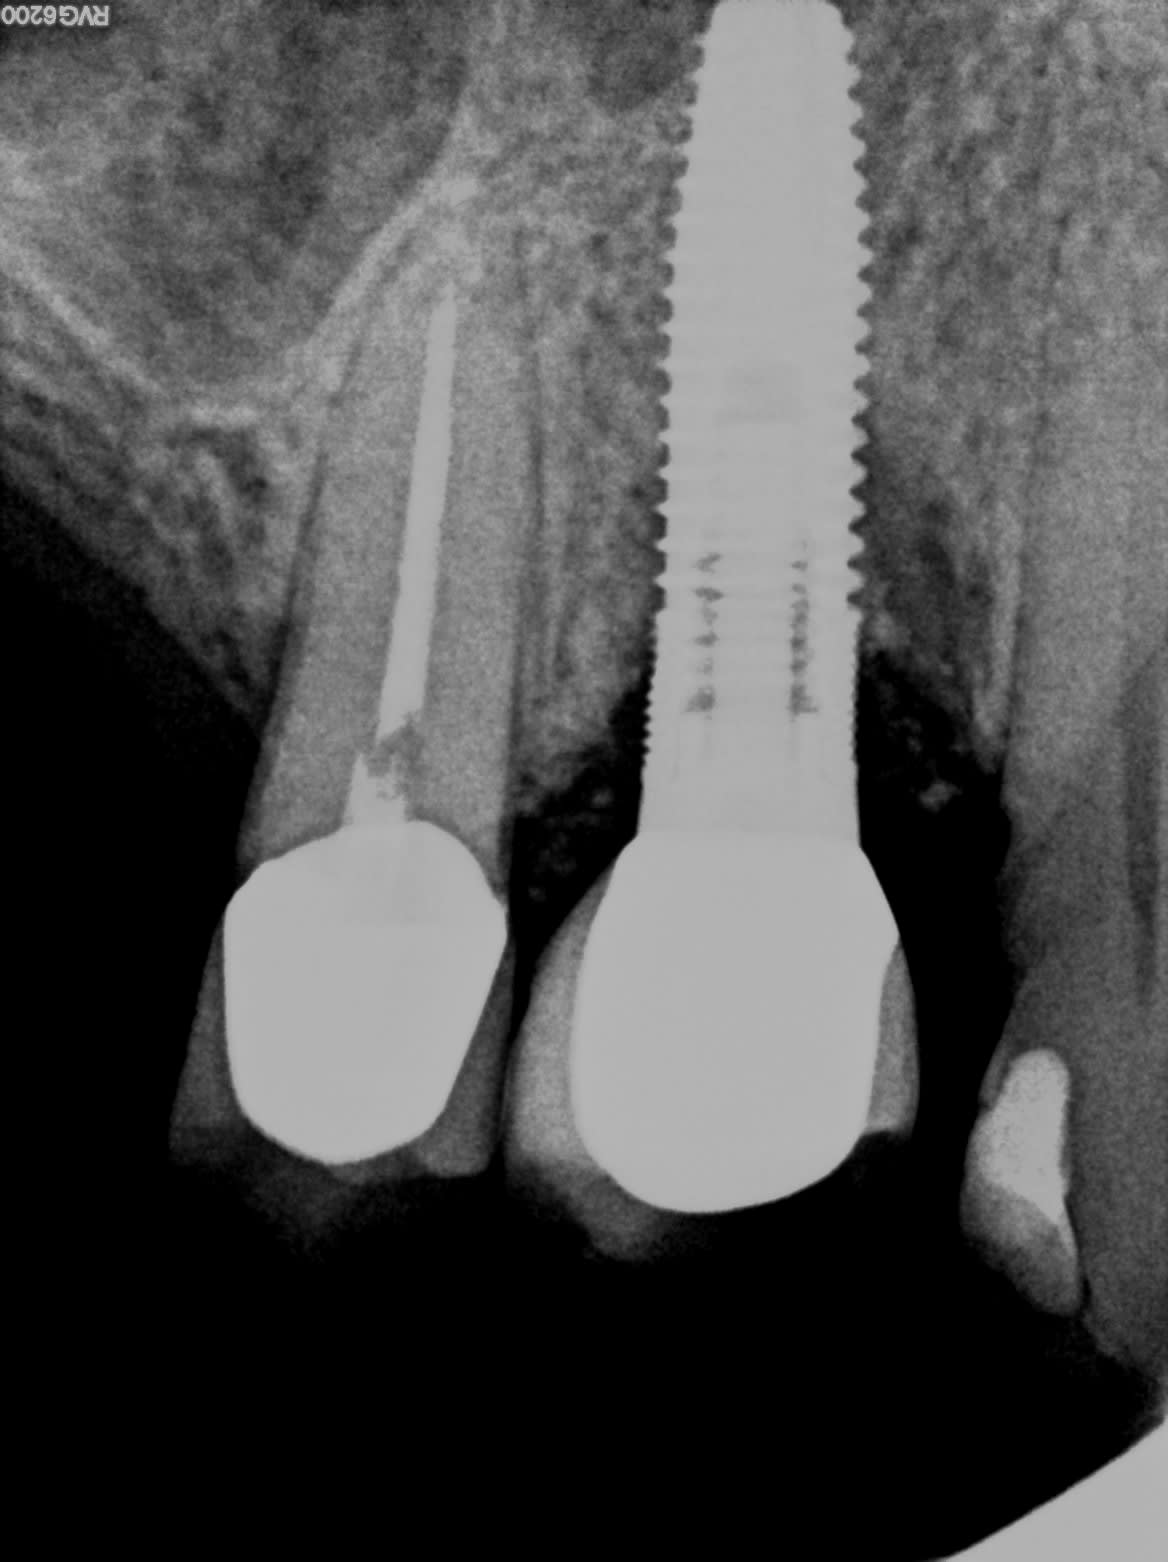

Quelqu'un saurait de quel implant il s'agit?

- est-ce que la radio est bien orthogonale pour identifier la géométrie des spires =>oui

- est-ce que le contraste de la radio peut donner des indications sur le type de connexion de l’implant => non

- est-ce que la radio permet de voir l’intégralité de l’implant =>non

En attendant voici une autre radio recontrastée

Ça pourrait être un Nobel replace trilobe.

Sur la seconde radio le col de l’implant semble fracturé.

L’inflammation me semble sauter aux yeux sur la première radio, mais c’est pas ma partie ☝️

Honnêtement, je n'avais pas vu la fracture sur la première radio transmise